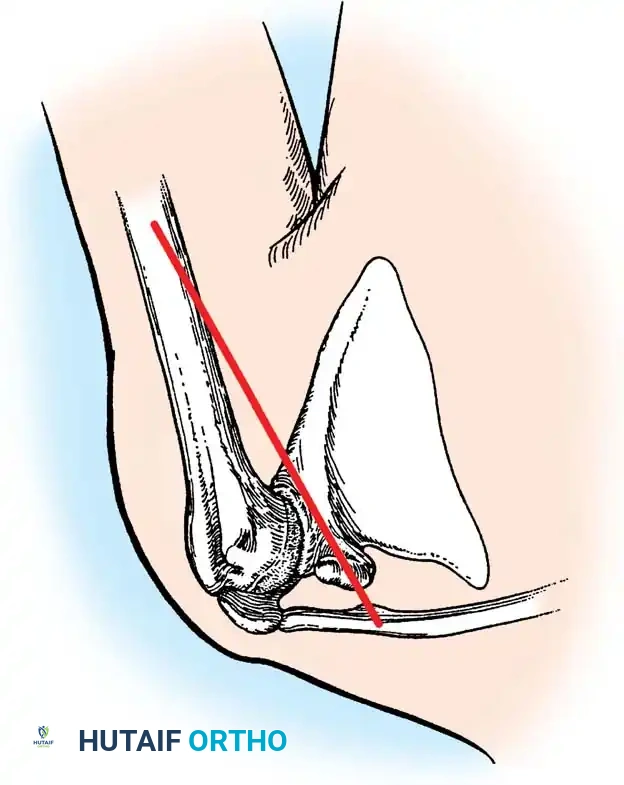

1. Positioning and Approach

The patient is placed in the lateral decubitus position with the arm draped over a bolster. A universal posterior approach is utilized.

- Ulnar Nerve Management: The ulnar nerve must be identified, mobilized, and protected throughout the procedure. Routine anterior transposition is performed at the conclusion of the case.

- Triceps Management: Several options exist, including a triceps-reflecting approach (Bryan-Morrey), a triceps-splitting approach, or a triceps-sparing approach. The Bryan-Morrey approach involves reflecting the triceps from medial to lateral in continuity with the anconeus and forearm fascia.

2. Joint Preparation

The tip of the olecranon is excised to facilitate access to the medullary canal. The distal humerus is prepared by resecting the trochlea and capitellum, preserving the epicondyles if possible to maintain collateral ligament attachments (though less critical in linked designs).